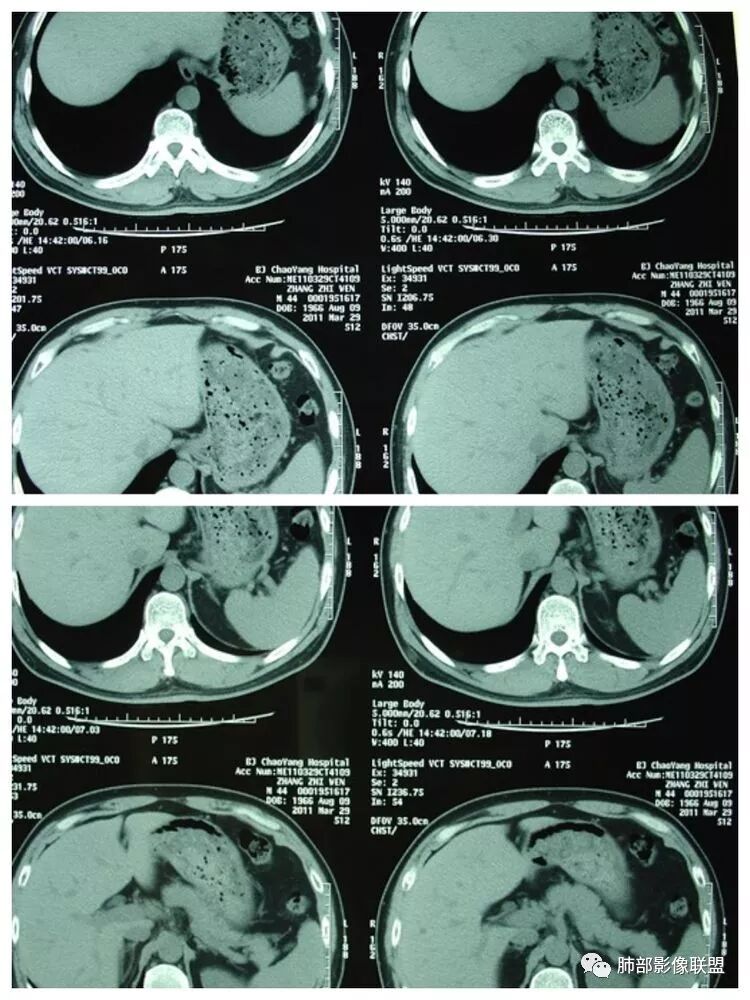

腹增强CT

南边:胸膜下,类圆形,边界清,内有坏死,典型的反晕征,支气管壁增厚不明显,支持血道来源脓毒栓子所致梗死、感染

血道来源没问题

左下叶大片类似病灶

脾大,肝内结节中央似有点状血管通过,炎性可能

2.本例应当属另一经典感染途径,肝脏感染,双肺脓毒性肺炎。大家都注意到患者的基础疾病,糖尿病。

4.本例肝脏的病灶并未出现典型肝脓肿图像特征,病灶密度及中央血管样结构显然不符合一般的囊肿。应当说,它是感染灶,但并未液化形成脓腔。